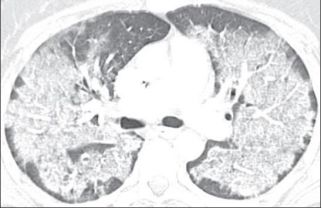

4.患者无发热,偶咳嗽,活动后气促,CT如下:

蝶羽征,这么多病灶,没有发烧,肺部感染可能性不大。

心力衰竭,做了心脏彩超没有任何依据。

什么情况?

行纤支镜,肺泡灌洗,结果:PAP。

PAP:肺泡蛋白沉着症。